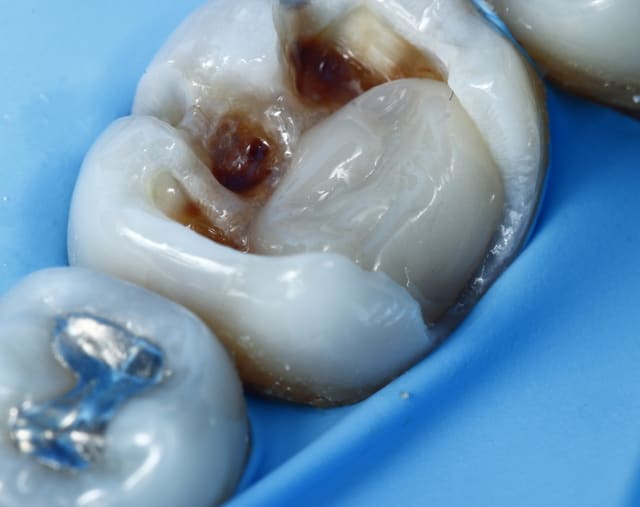

nic Tone en action ;)

--

Dr Cingulum

-----Ancien interné----

----Attaché à l'apex----

http://www.clinic-all.fr/ formation par passion